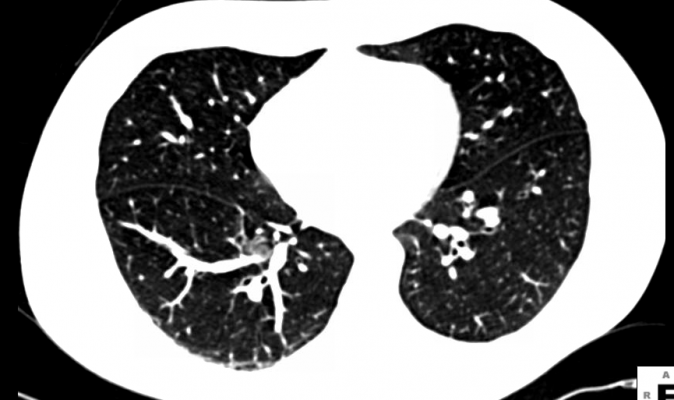

Understanding Your Chest CT Scan & PET Scan for Lung ... from www.docpanel.com The scan involves a specialized machine that takes multiple images of your lungs, known as slices. It gives detailed information about your cancer. Mri of the brain to look for metastases to the brain. Learn how doctors choose which technique to use. An ldct scan is the recommended screening test for lung cancer.the u.s. A chest ct scan can detect even smaller nodules in the lung. These slices are then put together to form a full picture of your lungs for radiologists to evaluate. A ct scan can be wrong:

A ct scan can detect potential cancer in a lung. Ct scan of the abdomen to check for spread to the liver or adrenal glands. Computed tomography (ct) scans detect tumors, but do not determine whether they are malignant or not. Learn how doctors choose which technique to use. Imaging tests usually can't tell if a change has been caused by cancer. Low dose ct scanning for lung cancer can detect lung cancer at an earlier, more treatable, stage, or rule out the presence of cancer entirely, as in the images above. Lung cancer screening is recommended for older adults who are longtime smokers and who don't have any signs or symptoms of lung cancer. It is used to look for early signs of lung cancer. Also, this imaging technique can show masses that might have developed as a result of lung cancer spread. A lung pet scan is typically combined with a lung ct scan to detect conditions like lung cancer. Initial identification of lung cancer in asymptomatic patients usually occurs on chest radiography or chest computed tomography (ct). The scan looks at your lungs and other parts of your chest. Radiologists use both ct and mri to detect and monitor cancer.

Ct scan a ct scan reveals the anatomy of the lungs and surrounding tissues, which our cancer doctors use to diagnose and monitor tumor growth.

Imaging tests usually can't tell if a change has been caused by cancer. The risk of developing lung cancer due to a single ct scan of the chest is estimated to be one in 10,000. Ct scan catches 70% of lung cancers at early stage, nhs study finds. If neurological symptoms have developed, a ct scan of the brain may be performed to check for metastases. A chest ct scan can detect even smaller nodules in the lung. It can also show whether the cancer has spread outside the lung. Magnetic resonance imaging (mri) the mri uses magnets to detect and diagnose cancers. Ct scan of the abdomen to check for spread to the liver or adrenal glands. These slices are then put together to form a full picture of your lungs for radiologists to evaluate. Scans give doctors the ability to diagnose lung cancer in the earliest stages, which allows for a better cure rate. The scan only takes a few minutes and is not painful. The scan involves a specialized machine that takes multiple images of your lungs, known as slices. Initial identification of lung cancer in asymptomatic patients usually occurs on chest radiography or chest computed tomography (ct).